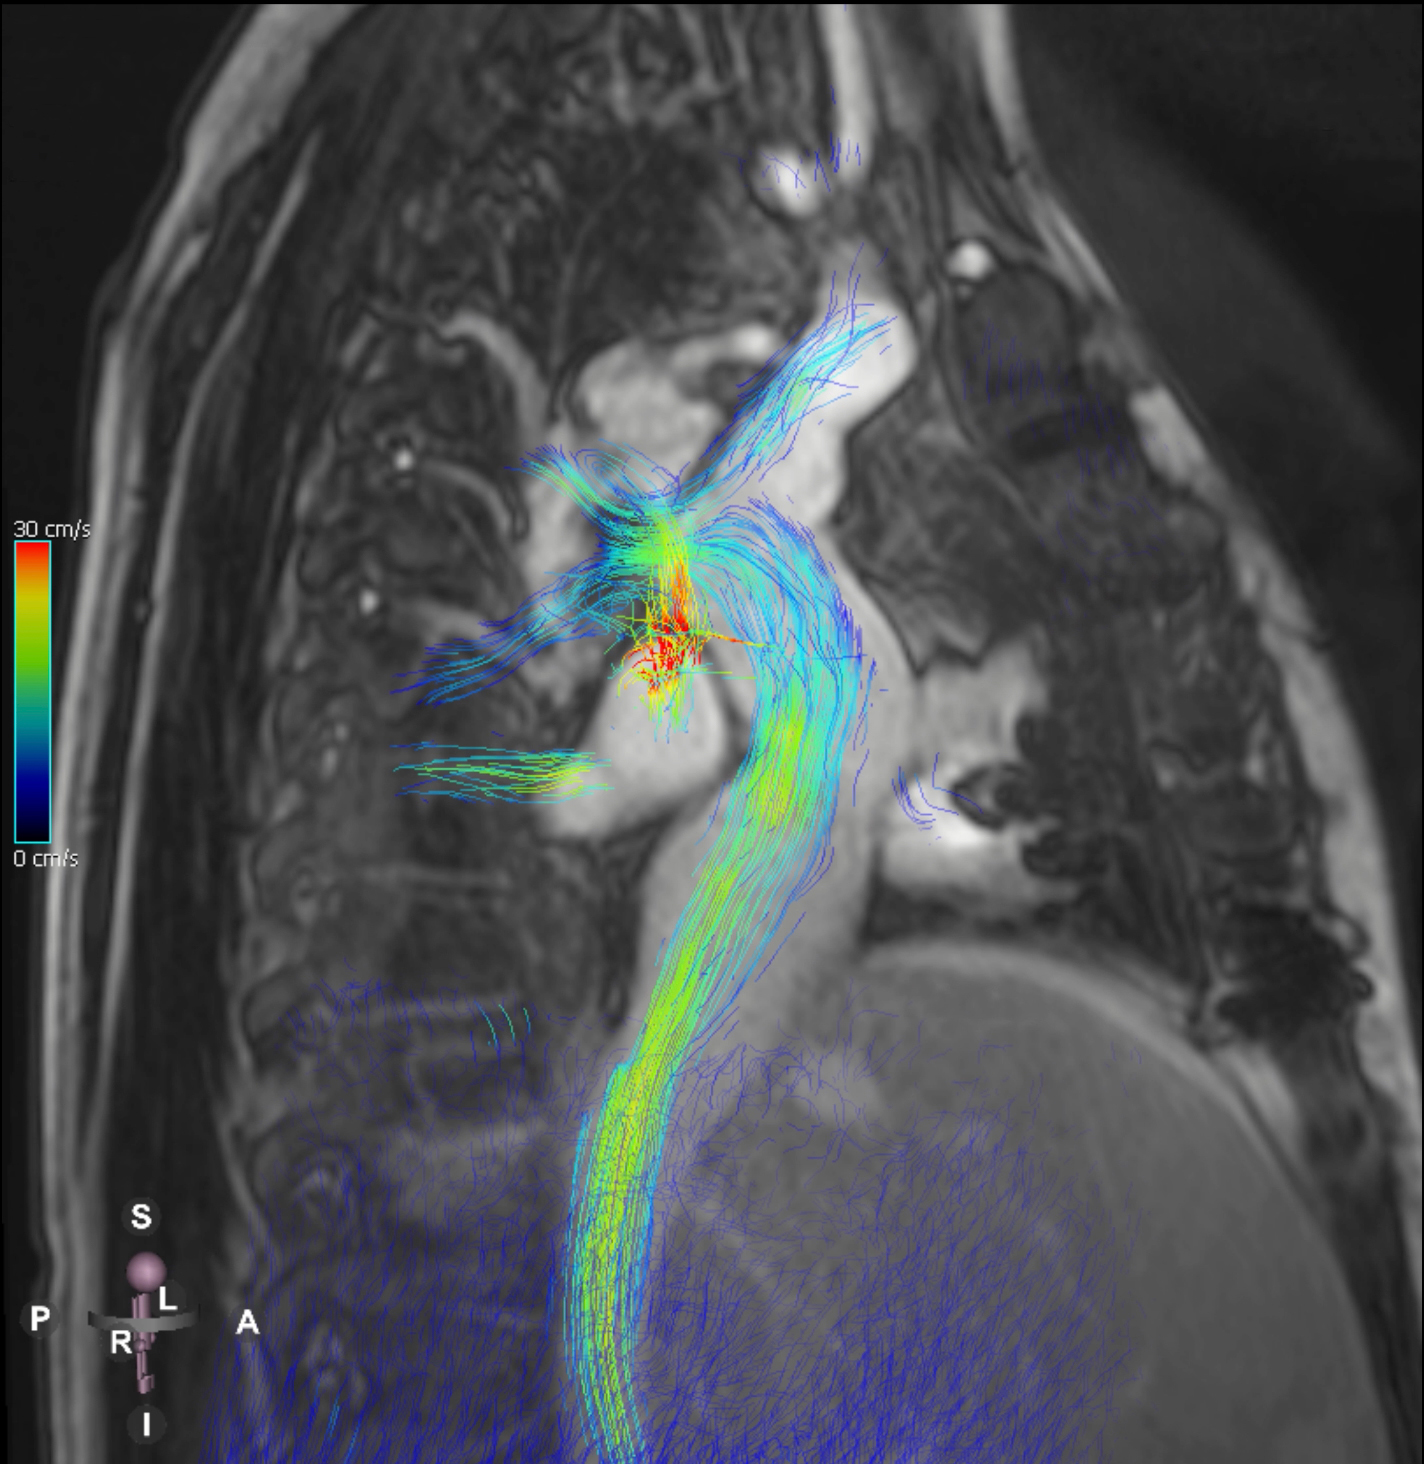

Diagnostic Techniques and Their Most Important Findings: Transthoracic echocardiography revealed preserved left ventricular systolic function (EF 60%), with a patent fenestration and no significant valvular disease, but with pleural effusion and ascites. Contrast-enhanced cardiovascular magnetic resonance (CMR) with angiography and 4D flow (Figure 1) demonstrated:

Figure 1. Fontan circulation assessed with 4D flow cardiovascular magnetic resonance.

Diagnostic Techniques and Their Most Important Findings: Transthoracic echocardiography revealed preserved left ventricular systolic function (EF 60%), with a patent fenestration and no significant valvular disease, but with pleural effusion and ascites. Contrast-enhanced cardiovascular magnetic resonance (CMR) with angiography and 4D flow (Figure 1) demonstrated:

- Pulmonary atresia with intact ventricular septum.

- Extracardiac Fontan conduit with concentric thickening, slow flow, and patent fenestration.

- Large secundum atrial septal defect (15 mm).

- Coronary fistula from the right coronary artery to the right ventricle.

- Mildly reduced left ventricular ejection fraction (47%).

- Congestive hepatopathy with splenomegaly and recanalized umbilical vein.

- Type 3 thoracic lymphatic perfusion pattern on T2-weighted sequences, indicating mediastinal and supraclavicular lymphatic involvement with extension into the mediastinum.

Figure 1. Fontan circulation assessed with 4D flow cardiovascular magnetic resonance.